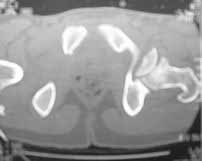

Male 22 yrs of age, RTA, front seat passenger in a truck. Sustained grade IIIB fracture of Tibia, and a Posterior dislocation of the Ipsilateral Left Hip.

Emergent closed reduction performed, and Tibial wound debrided. Next day Exfix applied and fibula plated. Initially femoral head fracture was not appreciated and it was thought that this is a posterior wall fracture. Presently two weeks down the line, Tibial wound is better but not completely healthy. and plastics want to wait for another five days, before they flap it. I enclose radiographs, Judet view, Ct scans in this and following mails.

2)The femoral head fracture involves the anter-inferior part and not the weight bearing superior dome. Also while moving the hip after taking weight off the traction, it does seem pretty stable. Should it be fixed even then?

I'd remove the displaced and malrotated head fragment, clean it on the back table, apply 2 or 3 glide holes, then clean the hip joint of debris, look at the acetabular fracture thru the joint and assure that it hasn't further displaced.

Based on the selected images that you shared with us, I would not leave it as is. The fragment is significant in terms of its size and location and displacement.